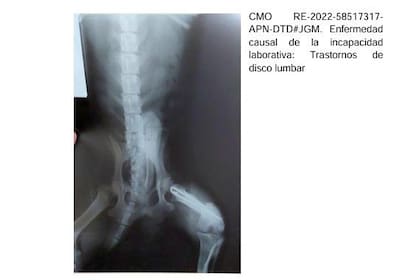

En la muestra auditada de más de 2500 pensiones, la agencia anuló las que habían sido otorgadas irregularmente; incluían expedientes en los que la radiografía de un perro acompañaba el certificado médico por un trastorno de disco lumbar emitido por un médico de Corrientes. En Chaco, con la misma radiografía de hombro se justificaron 150 pensiones por invalidez.